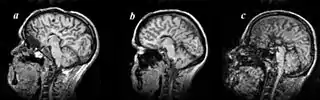

MRI images of three patients in the sagittal plane. A and B: Complete agenesis of the corpus callosum. C: Complete agenesis of both the corpus callosum and the anterior commissure.

Agenesis of the corpus callosum (ACC) is a rare birth defect in which there is a complete or partial absence of the corpus callosum. It occurs when the development of the corpus callosum, the band of white matter connecting the two hemispheres in the brain, in the embryo is disrupted. The result of this is that the fibers that would otherwise form the corpus callosum are instead longitudinally oriented along the ipsilateral ventricular wall and form structures called Probst bundles.